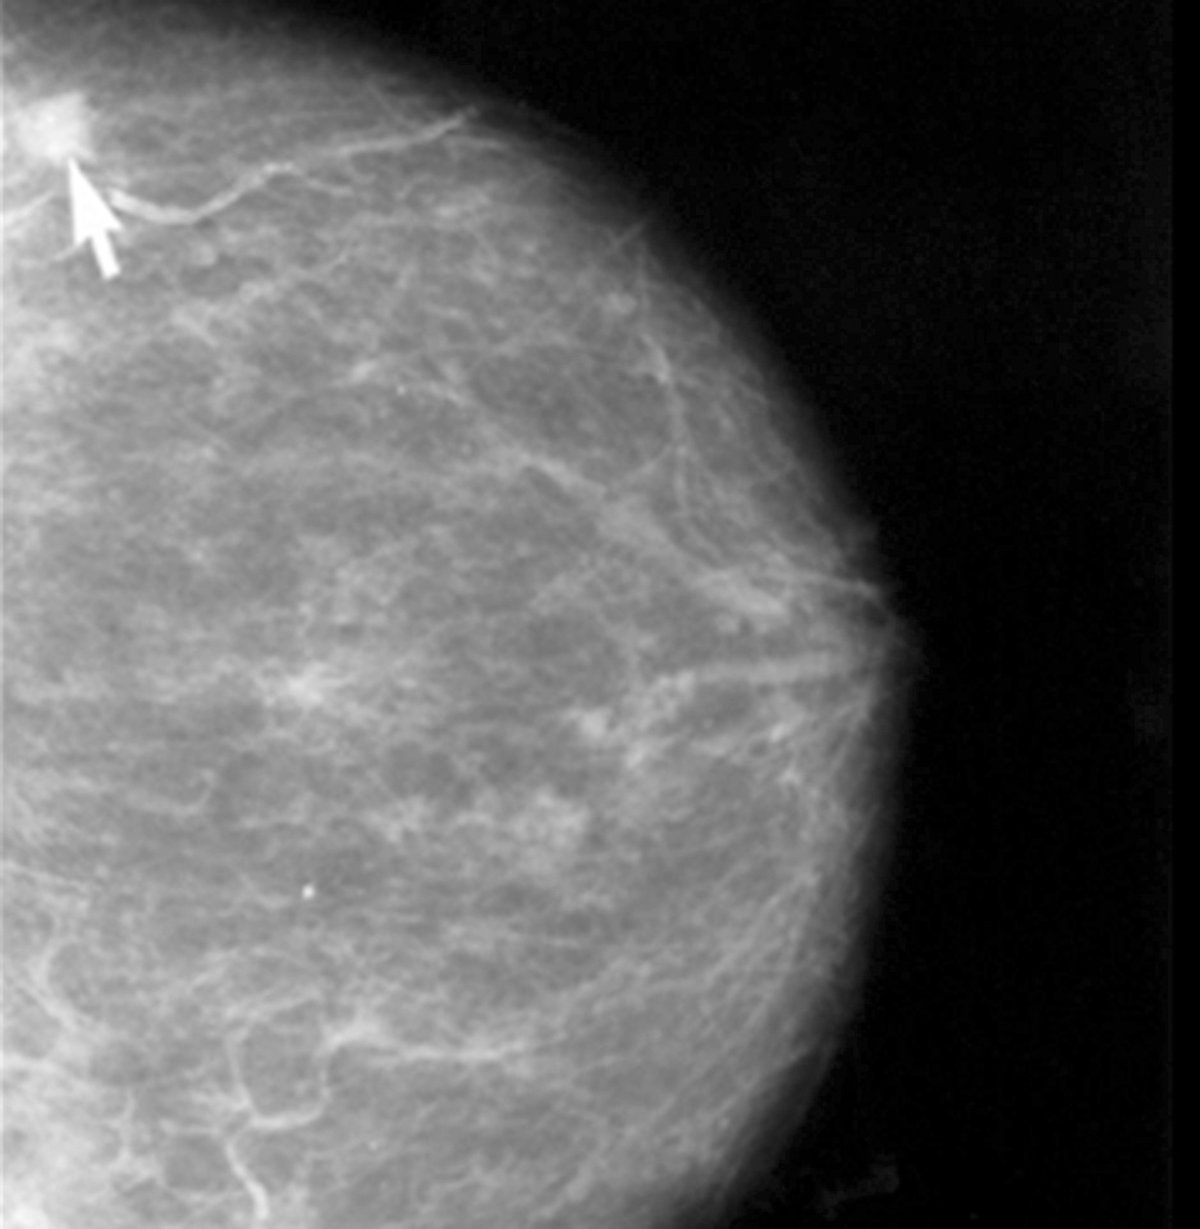

Alrededor de 2.100 de los 22.000 nuevos casos de cáncer de mama que se registran cada año en España se diagnostican en la Comunitat Valenciana, lo que supone algo más del 10 por ciento. En la mayoría de los casos se diagnostican en las 29 Unidades de Diagnóstico Precoz de las que se dispone en la autonomía, según los datos facilitados a raíz de la segunda reunión regional multidisciplinar del grupo SOLTI, dedicada al 'Abordaje multidisciplinar del tratamiento neoadyuvante del cáncer de mama'.

Gracias al trabajo de las 29 Unidades de Diagnóstico Precoz, de las mejoras en la cirugía, el tratamiento y también a la labor de las cinco Unidades de Consejo Genético de la Comunidad Valenciana, donde son visitadas aquellas familias con riesgo de presentar cáncer de mama hereditario, "la mortalidad por cáncer de mama en la Comunidad se ha reducido en torno a un 30 por ciento" en la última década, ha subrayado el doctor Gavilá.